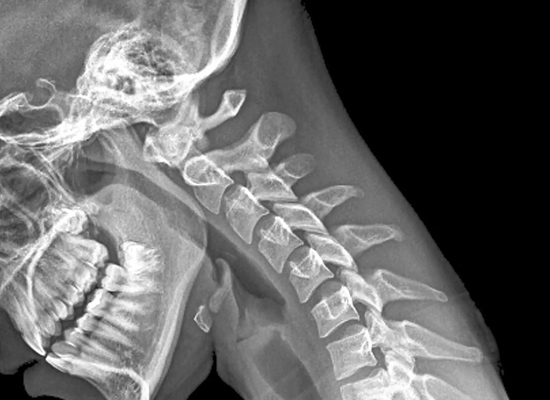

Contamos con equipos de rayos x digitalizados para la realización de cualquier estudio Radiologico como son:

• Radiografía de Cabeza y Cuello